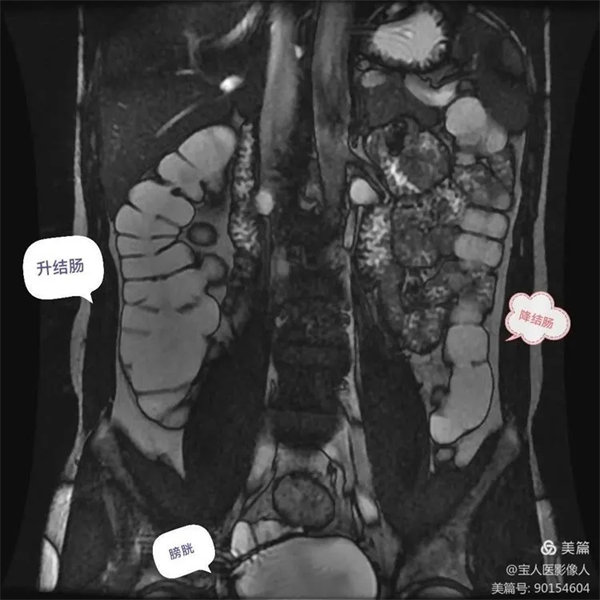

圖7:升、降結腸充盈顯示良好,結腸袋清楚,腸壁光滑,厚薄均勻,在腸液和周圍脂肪高信號之間對比鮮明。